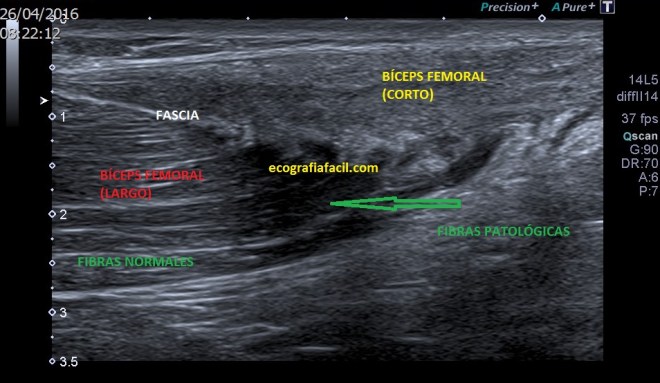

Este es el Bíceps Femoral en un corte superior al de la inserción en el Tercio Distal del Fémur, vemos la parte más superficial de la imagen la porción corta del músculo, desestructurada, heterogénea en su parte distal, más normal en la parte proximalmás profundo vemos la porción larga del Bíceps, más grande, separados por la Fascia, esta porción larga del B.F. tiene fibras normales y fibras afectadas, más hipoecogénicas, marcadas por una flecha verde, y la Fascia de separación de ambos, también afectada…Patología…Compara ahora con la Normalidad de la imagen siguiente:

Normal

Ves el Bíceps Femoral hipoecogénico (normal) que termina en forma de cuchillo (normal), superficial el Tendón de la porción corta del Bíceps Femoral, hiperecogénico y homogéneo (normal)…